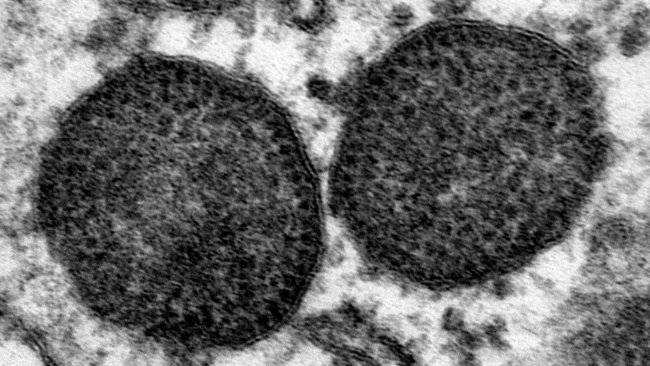

Detectado circovirus PCV3 em porcos com inflamação cardíaca

PCV3: novo circovírus suíno associado ao PDNS e falha reprodutiva